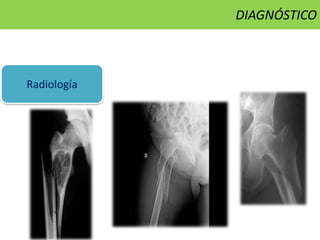

DIAGNÓSTICO

Radiología